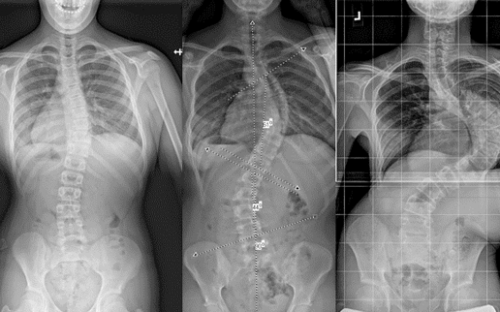

فشل الحزام يعني أنّ زاوية الاعوجاج (Cobb angle) لم تتحسن أو ازدادت بالرغم من الالتزام بارتدائه. الهدف الأساسي للحزام هو تقليل الانحناء، لذلك يعتبر فاشلًا عندما:

لا يحقق نسبة التصحيح المطلوبة داخل الحزام (In-brace correction).

1) عدم تحقيق التصحيح المطلوب على الأشعة داخل الحزام

40–60% تصحيحًا على الأقل داخل الحزام في أغلب الحالات المراهقية.

2) استمرار زيادة زاوية الاعوجاج مع المتابعة

حتى لو كان الطفل ملتزمًا بارتداء الحزام، إذا ارتفع الانحناء أكثر من 5 درجات خلال 6 أشهر فهذا مؤشر واضح على فشل الحزام.

زيادة الانحناء أكثر من 5 درجات في الأشعة الأخيرة

بروز الضلع أو زيادة الارتفاع الجانبي للجسم

إجراء أشعة داخل الحزام بعد 2–4 أسابيع من التسليم